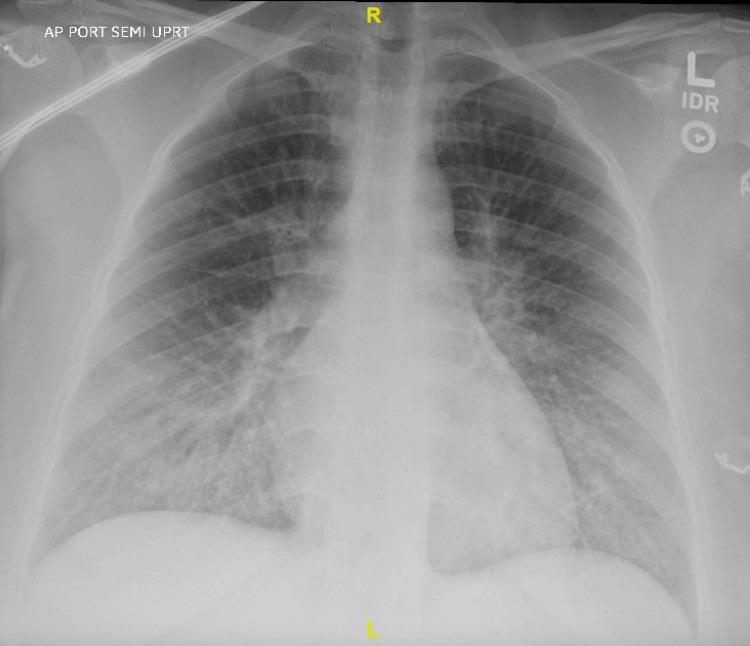

贝佐尔德-雅里什反射(BJR)是一种抑制性反射,其特征为源自心室机械感受器的心动过缓、低血压和呼吸暂停。BJR是神经轴索麻醉一种罕见但严重的并发症。我们报告一例33岁女性,在剖宫产术前接受腰麻-硬膜外联合麻醉时发生严重的BJR,从而采取了紧急措施。注射后几分钟内,她出现严重心动过缓(心率:17次/分钟)、低血压(收缩压:30多岁毫米汞柱)伴呼吸过缓(呼吸频率:6次/分钟),并接受了肾上腺素治疗。胎儿心动过缓促使进行紧急剖宫产。分娩后,患者出现室性心动过速,通过静脉输液和心脏监测进行治疗。患者和新生儿均在术后第4天病情稳定出院。该病例说明了神经轴索麻醉期间与BJR相关的母婴迅速出现的不良情况,以及迅速识别和治疗的必要性。关键步骤包括停止麻醉、静脉输液、左侧卧位、谨慎使用血管升压药、胎儿监测以及为紧急分娩做好准备。